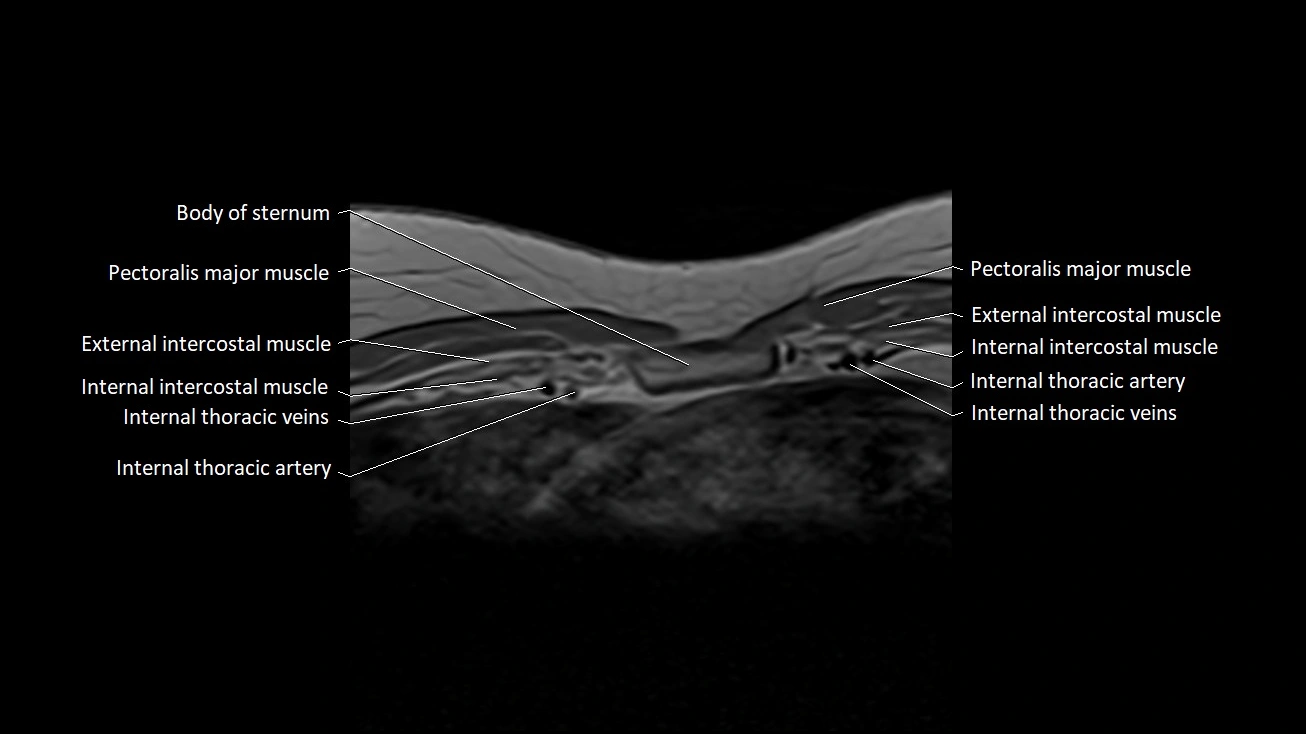

MRI images

image